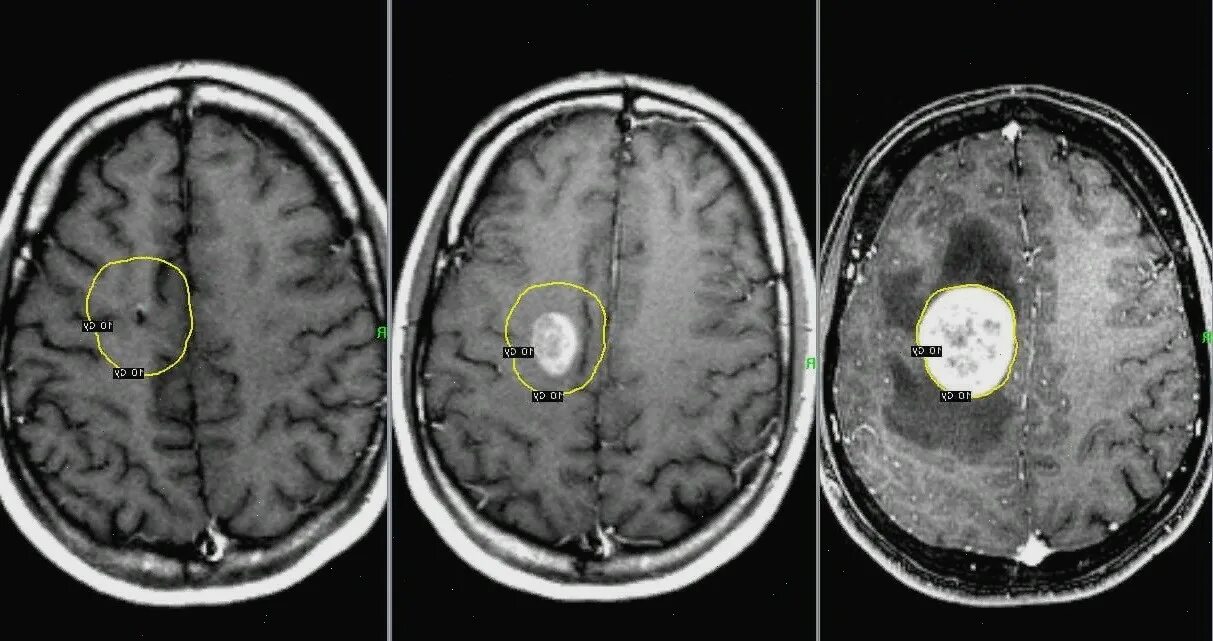

Как умирают от рака головного мозга